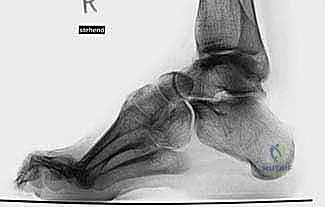

الشكل 1 • تشوهات القدم الجوفاء، منظر جانبي. لاحظ زيادة الانثناء الأخمصي لمقدمة ومنتصف القدم بالنسبة لمؤخرة القدم، وهو ما يسبب ضغطًا هائلاً على مشط القدم.

الأشعة السينية العادية (X-rays) أثناء الوقوف (Weight-bearing) هي الأساس. يقوم الدكتور هطيف بقياس زوايا محددة بدقة هندسية:

* زاوية ميري (Meary's Angle): لتقييم مدى تقوس منتصف القدم.

* زاوية ميل الكعب (Calcaneal Pitch Angle): تكون زائدة بشكل كبير في القدم الجوفاء.

* زاوية هيبس (Hibbs Angle): لتقييم التشوه في مقدمة القدم.